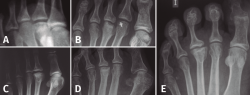

Figura 4. Estadios de Smillie. A: estadio I; B: estadio II; C: estadio III; D: estadio IV; E: estadio V.

Basándose en la historia natural de la enfermedad y atendiendo a los cambios radiológicos, Smillie(16) clasifica, con propósito terapéutico, la lesión en 5 estadios (Figura 4):

- Estadio 1: aparece una línea de fractura a través de la epífisis.

- Estadio 2: se produce una depresión central de la cabeza por colapso del hueso subcondral. El espacio articular puede ensancharse.

- Estadio 3: la depresión central hace que se proyecten hacia delante los bordes medial y lateral de la cabeza, manteniéndose intacta la parte plantar.

- Estadio 4: la parte central necrosada de la cabeza puede desprenderse de la parte plantar, formándose un cuerpo libre articular.

- Estadio 5: aplanamiento de la cabeza metatarsal y van apareciendo los cambios degenerativos secundarios.